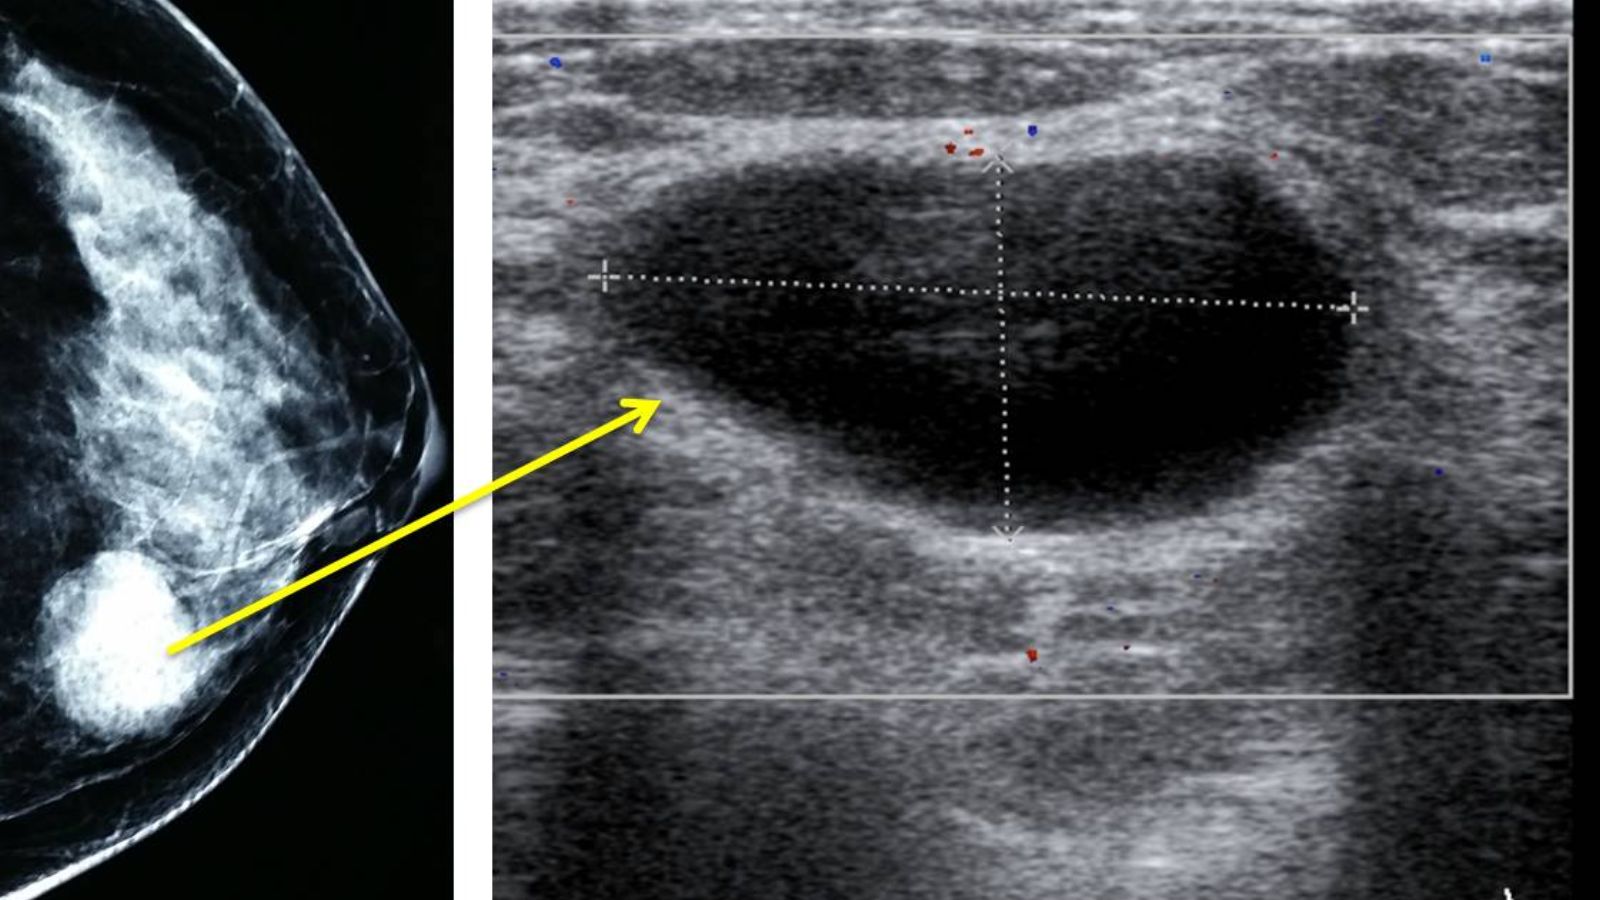

Đặc điểm trên siêu âm của nang tuyến vú

Khi siêu âm tuyến vú, các đặc điểm sau thường giúp bác sĩ nhận biết và đánh giá nang tuyến vú:

- Hình dạng: Nang vú thường có hình tròn hoặc oval, tùy thuộc vào kích thước và vị trí trong mô vú.

- Bờ nang: Bờ nang rõ ràng, mềm mại và phân định rõ ranh giới với các mô xung quanh.

- Âm học: Nang vú thường xuất hiện với hình ảnh trống âm (không phản xạ tín hiệu siêu âm), kèm theo hiện tượng tăng sáng phía sau, cho thấy nang chứa đầy dịch lỏng.

- Kích thước: Kích thước nang có thể thay đổi đáng kể, từ các nang nhỏ vài milimet đến các nang lớn có đường kính từ 2.5 cm đến 5 cm hoặc hơn.

Những đặc điểm này giúp bác sĩ dễ dàng phân biệt nang tuyến vú với các khối u đặc và đưa ra các chẩn đoán chính xác hơn.

Nang tuyến vú trên siêu âm giúp bác sĩ phân biệt chúng với các khối u khác